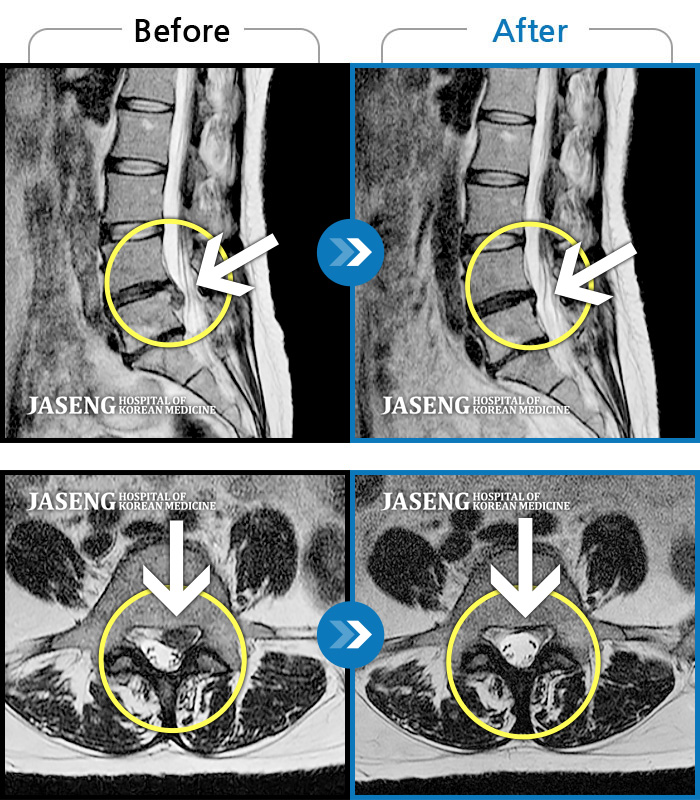

Before

After

환자에게 사전 동의를 받아 동일 조건에서 촬영되었습니다.

개인에 따라 치료 후 부작용이 발생할 수 있으니 의료진과 상담 후 치료를 진행하시기 바랍니다.

허리 숙일 때, 앉을 때, 보행시 허리 통증 증가, 좌측 발목~무릎부위 통증

허리와 골반 통증, 누워서 다리를 움직일 때 통증 발생